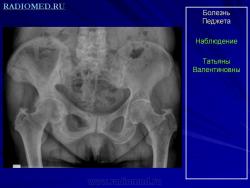

Болезнь Педжета проявляется у больных в возрасте старше 40 лет. Заболеваемость варьирует в пределах 0,1–3% населения. У лиц моложе 40 лет частота заболеваемости не превышает 0,5%, у лиц старше 90 лет частота заболеваемости около 10%. Деформирующий остоз чаще встречается у мужчин. Поражение только одной кости (монооссальная форма), преимущественно большеберцовой, бедренной, или таза встречается редко, в 85% в процесс вовлекается множество костей (длинные кости, кости таза, черепа и позвоночника) ― полиоссальная форма. В основном поражаются кости, несущие наибольшую механическую нагрузку (поясничные и крестцовые позвонки, бедренная и большеберцовые кости и др.); характерны поражения костей крыши черепа; из лицевых костей чаще поражаются челюсти.

Деформирующая остеодистрофия (болезнь Педжета) чаще проявляется у мужчин в возрасте 40-60 лет, характеризуется постепенно прогрессирующим утолщением коркового слоя костей с развитием гиперостозов, деформацией, искривлением костей, беспорядочностью их структуры, образованием в них кист; поражаются кости мозгового черепа, позвоночника и длинных трубча­тых костей. Размеры мозгового черепа увеличиваются, наружная пластинка костей свода черепа местами утолщена, гиперостозы чередуются с участка­ми беспорядочного разрежения кости. В связи с деформацией костных от­верстий и каналов основания черепа и межпозвонковых отверстий наруша­ется функция черепных и спинномозговых нервов, возможны расстройства кровообращения. Деформация глазниц обусловливает экзофтальм. Нередко отмечаются признаки внутричерепной гипертензии. Позвонки сплющены; в трубчатых костях сужены костномозговые каналы, возможны патологические переломы костей, при этом линия перелома четкая, ровная, как при переломе очищенного банана («банановый перелом»); усилены физиологические изгибы позвоночника. Процесс может быть относительно ограниченным или распро­страненным. Содержание кальция и фосфора в крови нормально или слегка увеличено, активность щелочной фосфатазы повышена. Предполагается доми­нантный тип наследования с различной экспрессивностью. Описал болезнь в 1877 г. английский хирург J. Paget (1814-1899).

Болезнь Педжета.

Болезнь Педжета (БП) является довольно распространенным заболеванием во многих европейских странах, США. Оценка распространенности у людей старше 55 лет колебалась от 2% до 5%. Факт, что значительная доля пациентов остаются бессимптомными на протяжении всей их жизни. БП всегда следует рассматривать в дифференциальной диагностике остеосклеротических, а также остеолитических скелетных поражений.